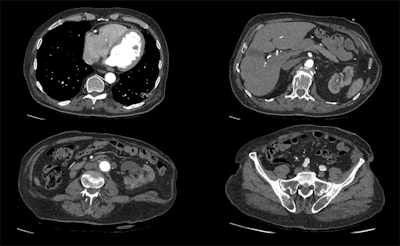

A 100-kV CT scan with a dose length product of 159.8 mGy.cm, using Canon's Advanced Intelligent Clear-IQ Engine (AiCE). Images are courtesy of Radboud UMC, Nijmegen, the Netherlands, and originally appeared in ECR Today on 1 March 2019.

A 100-kV CT scan with a dose length product of 159.8 mGy.cm, using Canon's Advanced Intelligent Clear-IQ Engine (AiCE). Images are courtesy of Radboud UMC, Nijmegen, the Netherlands, and originally appeared in ECR Today on 1 March 2019.Luminaries also noted that rigorous clinical validation of AI algorithms remains an important obstacle for widespread acceptance and deployment of AI for image analysis applications in clinical practice. Developers need to demonstrate in prospective studies that their algorithms can yield high levels of performance on images generated by equipment of different vendors and in different patient populations -- not just on the images on which they were trained.